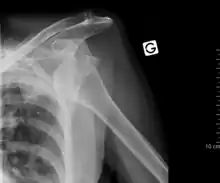

An inferior dislocation of the shoulder after an automobile accident. Note how the humerus is abducted. Also present is a fracture of the greater tuberosity.

Inferior dislocation is the least likely, occurring in less than 1%. This condition is also called luxatio erecta because the arm appears to be permanently held upward or behind the head.[14] It is caused by a hyper abduction of the arm that forces the humeral head against the acromion.[15] Such injuries have a high complication rate as many vascular, neurological, tendon, and ligament injuries are likely to occur from this mechanism of injury.